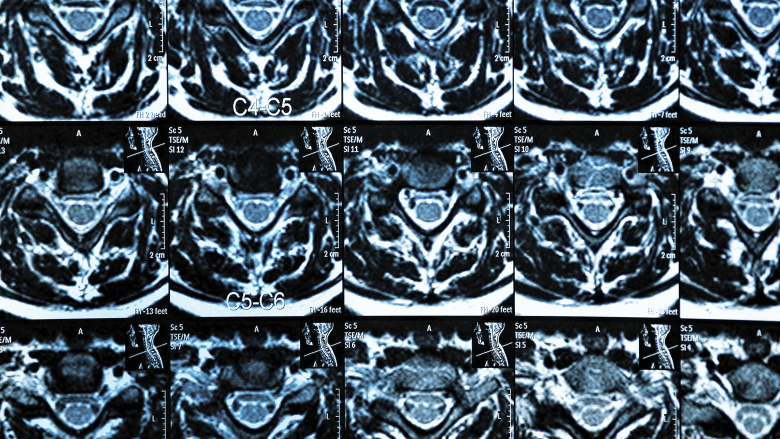

MRI scan of the cervical spine showing multiple spinal segments

Magnetic resonance imaging (MRI) is a powerful diagnostic tool used to evaluate spine pathology.